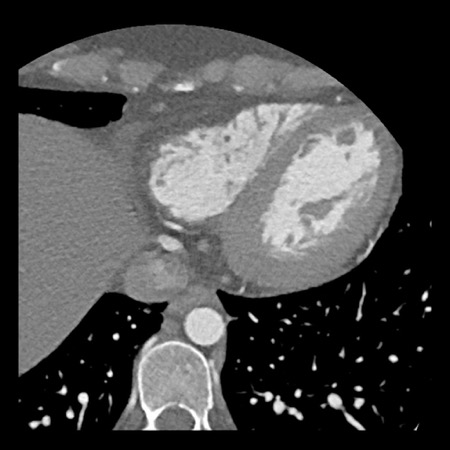

case 1 – CAD-RADS 2/P1

First, scroll through the scan.

Not all images are included. Some images without any abnormalities are skipped

from the series.

How would you describe the findings on the coronary CTA?

The findings are:

- Agatston score of

this patient was 14 (P1). Please, also note the calcification of the aortic valve. - Some partially

calcified and calcified plaques are present in the LAD with mild stenosis

(25-49%). - Calcified-plaque in

the LCX causing minimal stenosis (<25%). - Non-calcified

plaque in the distal RCA causing minimal stenosis (<25%). - This patient classifies

as CAD-RADS 2/P1, which means no further workup is needed.